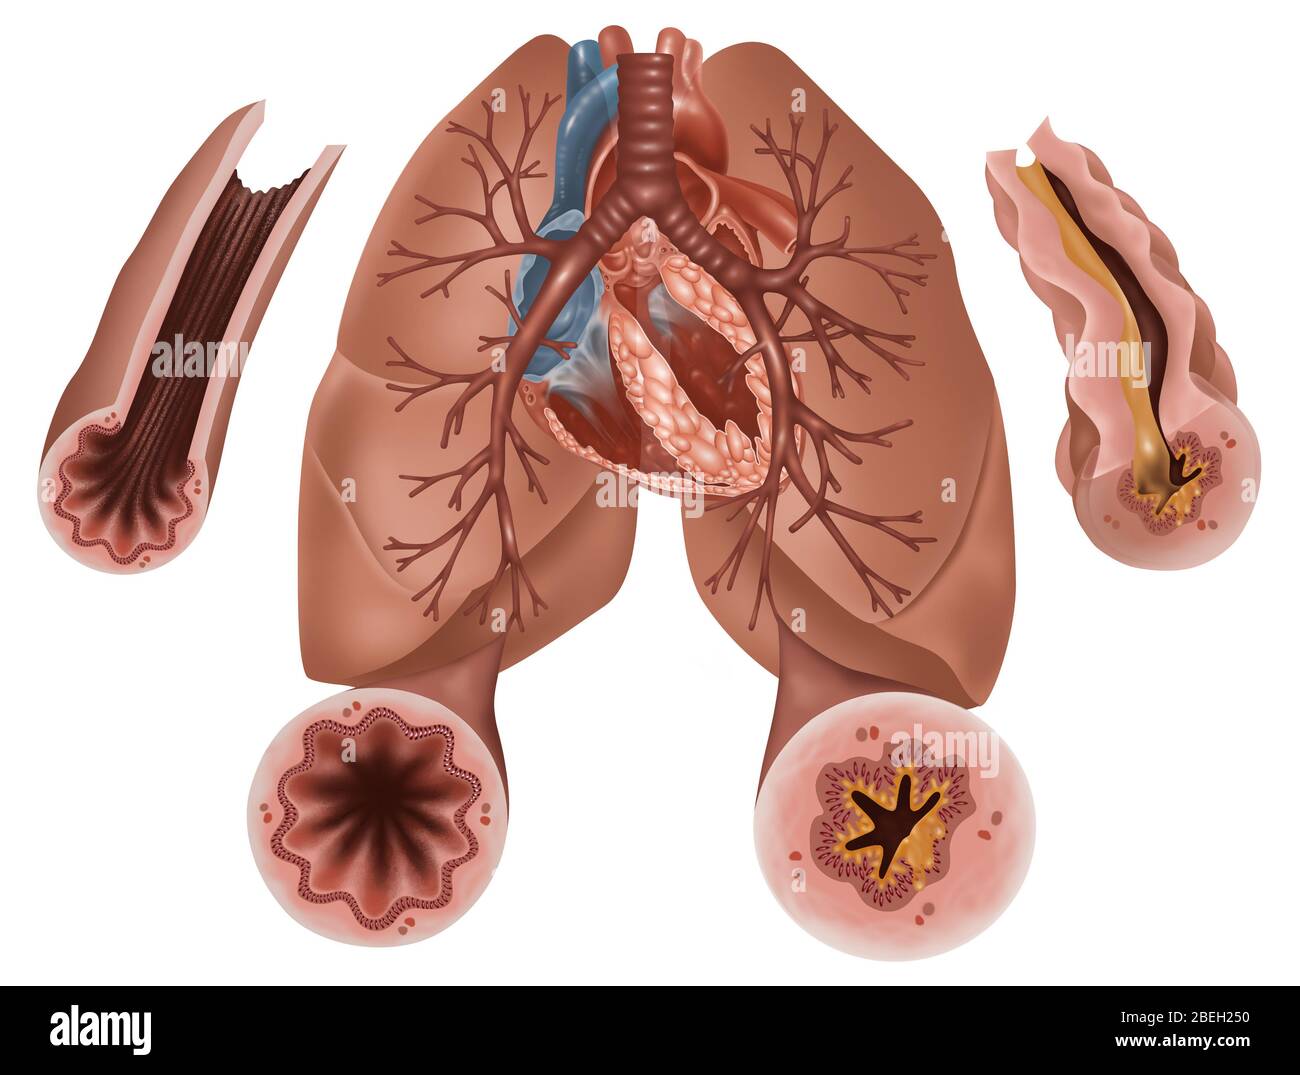

COPD (Chronic Obstructive Pulmonary Disease) Stock Vectorhttps://www.alamy.com/image-license-details/?v=1https://www.alamy.com/copd-chronic-obstructive-pulmonary-disease-image236623748.html

COPD (Chronic Obstructive Pulmonary Disease) Stock Vectorhttps://www.alamy.com/image-license-details/?v=1https://www.alamy.com/copd-chronic-obstructive-pulmonary-disease-image236623748.htmlRFRMY404–COPD (Chronic Obstructive Pulmonary Disease)

COPD (Chronic Obstructive Pulmonary Disease) Stock Vectorhttps://www.alamy.com/image-license-details/?v=1https://www.alamy.com/copd-chronic-obstructive-pulmonary-disease-image236623790.html

COPD (Chronic Obstructive Pulmonary Disease) Stock Vectorhttps://www.alamy.com/image-license-details/?v=1https://www.alamy.com/copd-chronic-obstructive-pulmonary-disease-image236623790.htmlRFRMY41J–COPD (Chronic Obstructive Pulmonary Disease)